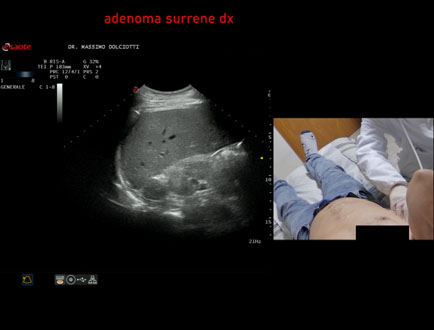

Data inserimento: 06/11/2025

Ecografia del: 31/10/2025

Strumento: Esaote MyLab Eight

Sonda: Convex Multifrequenza 1-8 MHz

Età Paziente: F 69 anni

Motivazione dell'esame: follow up per piccolo adenoma surrenalico.

Commento all'esame: le immagini ed il video documentano in sede surrenalica destra, formazione ipoecogena, a margini definiti, rotondeggiante, delle dimensioni di 15,8 x 14,8 mm, da ricondurre ad adenoma surrenalico.

Conclusioni: piccolo adenoma surrenalico destro (small right adrenal adenoma).

Presentazione: Dr. Massimo Dolciotti - Ancona

Elaborazione digitale: Andrea Dini - Ancona